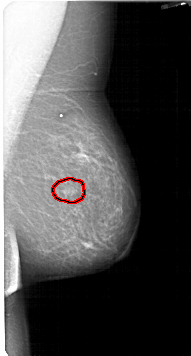

A_1435_1.LEFT_CC

LEFT_CC LINES 5311 PIXELS_PER_LINE 2746 BITS_PER_PIXEL 12 RESOLUTION 43.5 OVERLAY

FILE: A_1435_1.LEFT_CC.OVERLAY

TOTAL_ABNORMALITIES 1

ABNORMALITY 1

LESION_TYPE MASS SHAPE OVAL MARGINS ILL_DEFINED

ASSESSMENT 4

SUBTLETY 3

PATHOLOGY BENIGN

TOTAL_OUTLINES 1

BOUNDARY